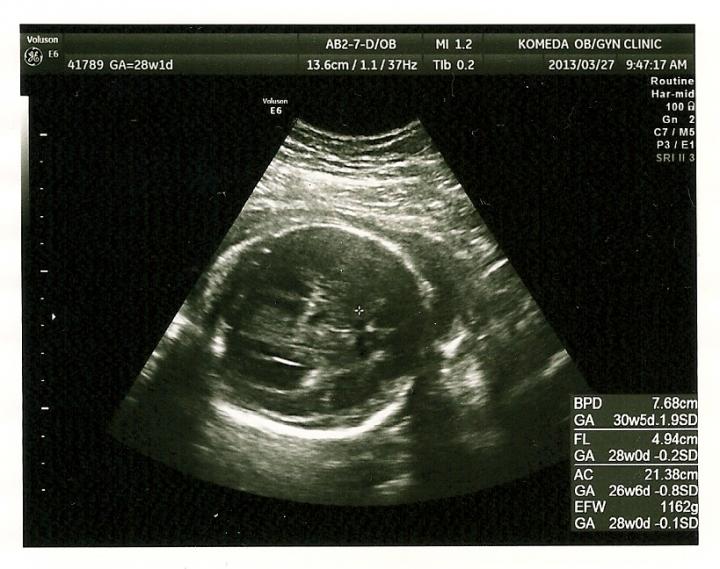

しっかり逆子もなおっており、赤ちゃんの体重も 1162g